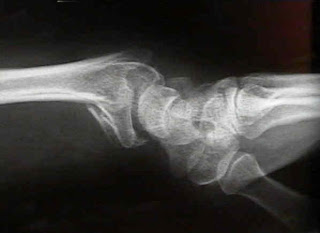

Wrist | Radiology Key

Wrist | Radiology Key from radiologykey.com